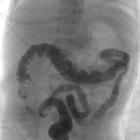

Radiograph

May show multiple dilated bowel loops which are a non-specific finding. There may be a caliber change around the splenic flexure.

Fluoroscopy: contrast enema

Contrast enema may demonstrate a small caliber to the left colon with multiple filling defects within due to retained meconium. The rectum is usually normal in size, unlike Hirschsprung disease. The use of high osmolar ionic contrast media for enema in a neonate or infant is controversial due to the risks associated with fluid shift . The enema can be both diagnostic as well as therapeutic and is usually accompanied by the passage of meconium during or after the procedure.